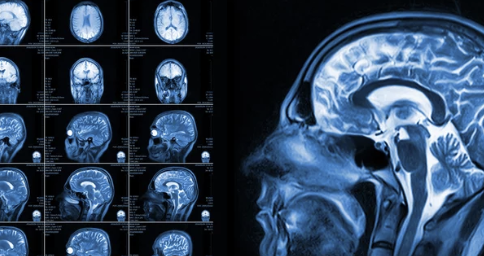

1. MRI 검사란?

MRI(Magnetic Resonance Imaging, 자기공명영상)는 강한 자기장을 이용해 인체 내부를 정밀하게 촬영하는 검사로, 방사선 노출 없이 장기나 관절, 신경 등을 자세히 확인할 수 있는 장점이 있다.